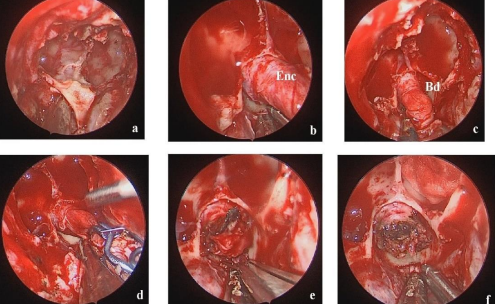

The repair of the encephalocele was performed using an endoscopic endonasal approach. the sac was resected at the most distal part after being coagulated. We have performed a usual an endoscopic enodonasal binostril approach. After the sphenoidotomy , we can appreciate the bony borders extensions of the encephalocele the long of the sellar floor (image a - figure 2). The sac of was dissected 360 degrees from the bony defect that was individualized clearly. after clipping the lower extremity of the malformation we have tried first to puncture it sing a syringe to reduce tension inside the sac without getting CSF.  we have coagulated and sectioned it just superior to the vascular clip.  the reconstruction of the bony defect was secured with double layers of fascialata and a nasoseptal flap that was harvested in the right nostril.

Figure 2: different important surgical steps .a- the endoscopic view of the encephalocele after the sphenoidotomy .b+c – the circumferential dissection of the sac and the definition of the bony borders of the defect .d- the most lower extremity of the sac was clipped using aneurysm clip to prevent eventual important CSF leaking after section during surgery  .e+f – section just distal to the clip and the final view of the treated malformation .